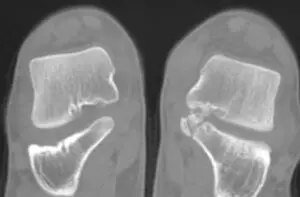

What is a Tarsal Coalition?talocalcaneal coalition

• Talocalcaneal Joint – the joint between talus and calcaneus bones.

Specific x-ray views can pick up tarsal coalitions. However, a CT scan is most accurate at identifying the specific location of the coalition.